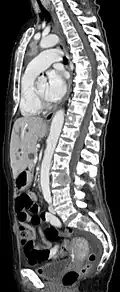

- Comparaison scanner/IRM pour des métastases ostéolytique d'un cancer du sein dans la colonne vertébrale

Scanner sagittal reconstruit, représentation dans la fenêtre osseuse. Comme la patiente avait des métastases dans toutes les régions du corps, elle ne pouvait pas lever les bras pour l'examen, ce pourquoi les mains sont présentées.

Scanner sagittale, parties molles. Outre les métastases dans la colonne vertébrale, qui envahissent en partie le canal médullaire vers l'arrière, métastases aussi dans le sternum. Plus des métastases dans le foie.